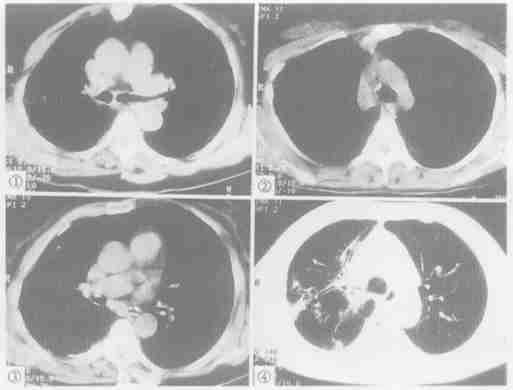

左主支氣管斷裂

右主支氣管撕裂

左主支氣管斷裂在縱隔胸膜外的支氣管斷裂,可造成縱氣腫

氣管撕裂如果縱隔胸膜沒有破裂,氣管斷裂僅引起縱隔氣腫病因

CT病理生理

胸CT2.氣管CT 斷層檢查 可發現氣管斷裂的直接徵象,氣管透亮帶的變形及不連續,甚至有錯位的徵象。